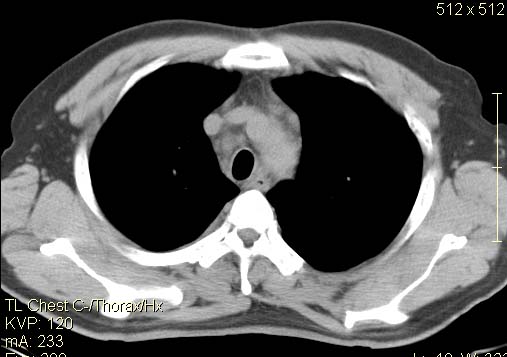

以下是引用qc80012345在2007-4-17 12:33:00的发言:[br]右肺下叶周围型肺癌伴肺门及纵隔内淋巴结转移;比较清楚。

以下是引用qingyuan在2007-4-17 14:19:00的发言:[br]右肺下叶外侧后段胸膜下区节结样病变、分叶、内可见空洞,壁厚薄不均,胸膜凹陷、肺门周围区纹理增粗、僵硬、并近似小结节样改变,肺门区软组织节结、纵膈淋巴结肿大,患者病史长、抗炎治疗无好转炎性改变基本排除,考虑:右肺下叶周围型肺癌伴纵膈及右肺门区淋巴结转移、肺内淋巴管受侵。